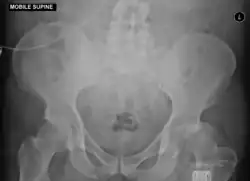

Anterior dislocation of the hip

Anterior-posterior (AP) X-rays of the pelvis, AP and lateral views of the femur (knee included) are ordered for diagnosis.[13] The size of the head of the femur is then compared across both sides of the pelvis. The affected femoral head will appear larger if the dislocation is anterior, and smaller if posterior.[14] A CT scan may also be ordered to clarify the fracture pattern.